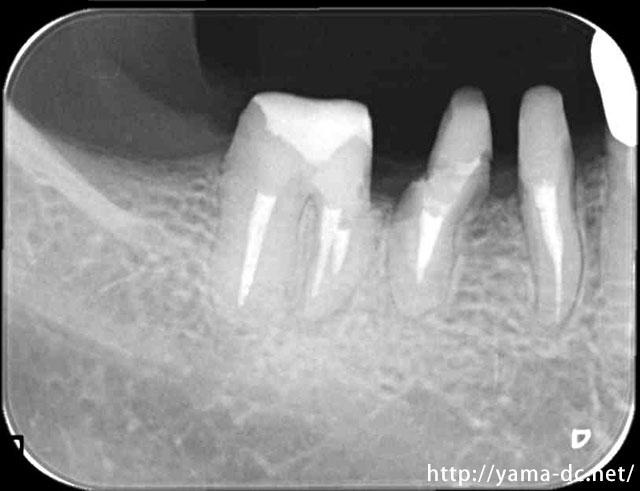

APF6か月後

歯周外科治療を行う事で歯ぐきと虫歯の治療がきちんと出来ている事が分かると思います。